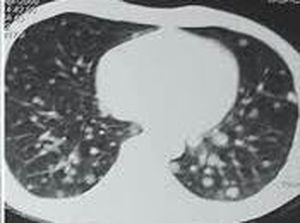

Secondary pulmonary metastasis, Primary tumors in the kidney, colon, or bladder that metastasize to the lungsmay sometimes be completely removed with surgery. In most cases, metastatic lung cancer can't be cured. However, treatments may help prolong your life and improve the quality of your life.